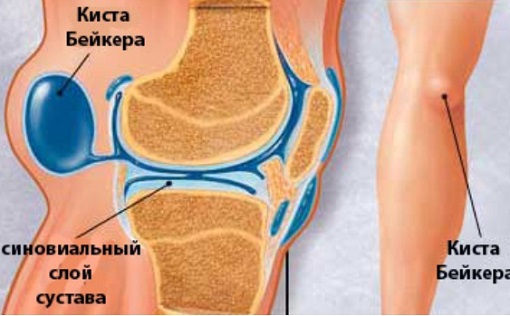

Фото и диагностика кисты Бейкера